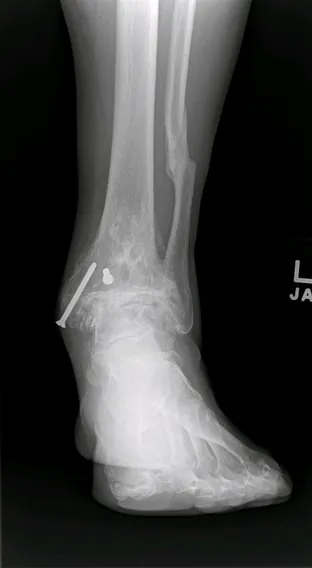

Ankle joint replacements are a reserved procedure for patients who meet certain criteria for functionality involving age, medical conditions, level of arthritis, and activity level, amongst others. The level of arthritis is typically severe and dibilitating as demonstrated in the x-ray image below. This person had a severe ankle fracture many years ago that was surgically repaired and later developed limiting arthritis to the point where they could no longer use their ankle because of pain. There is absence of joint space at the ankle joint along with remodeling of the bones around the ankle due to degeneration of the joint. The abnormal appearance of the thin bone called the fibula is a result of not fixing this bone when the patient had the original surgery.  This is referred to as malunion.

Pre and Post op Pics of Arthiitic Ankle S/P Total Ankle Replacement (TAR)

Preop, Intraop and Postop X-rays status post Total Ankle Replacement for Ankle Arthritis